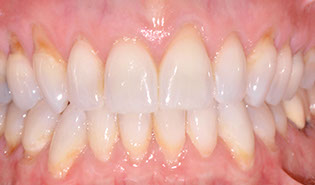

3.2 Immediate Load Prosthetics (All-on-4)

This part of the course covers the methods of diagnosis, practical treatment planning, pre-surgical prosthodontics, imaging, armamentarium, and clinical techniques needed for this exciting treatment modality. Crucial to this treatment modality is the understanding of the biomechanical aspects and functional loading of the immediate full arch prostheses. The aesthetic and phonetic requirements, space requirements, laboratory communication, insertion techniques post-operative follow-up and hygiene requirements are key to this treatment.